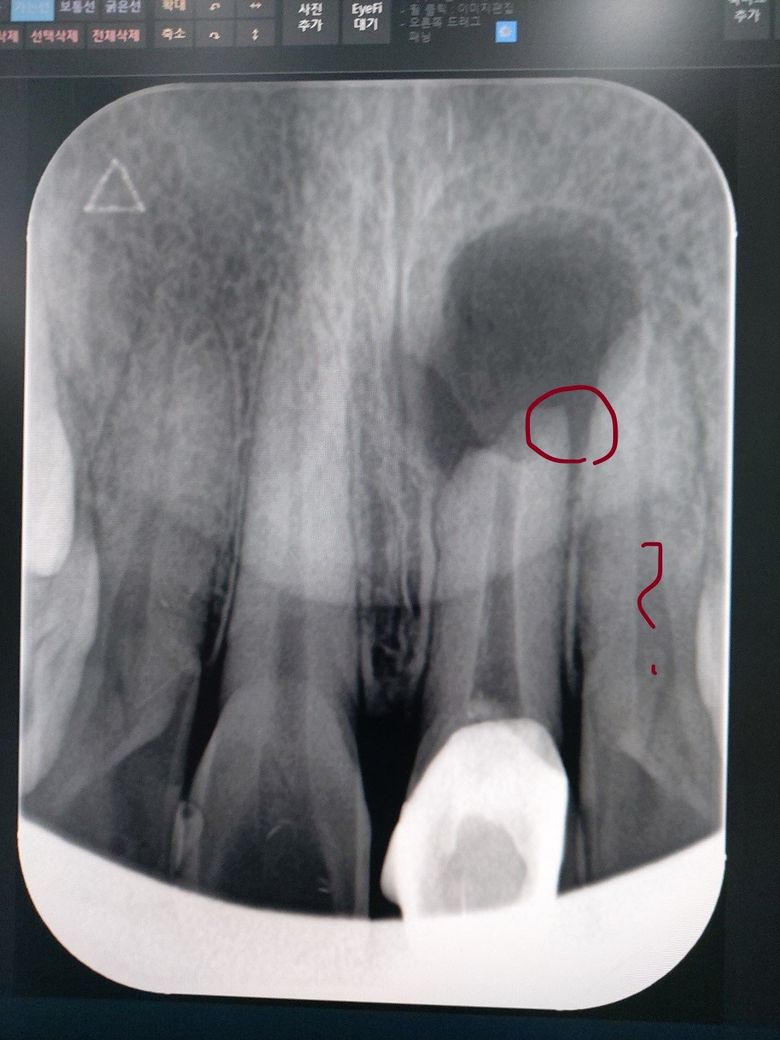

치근단염이 재발해서 좀 커졌는데 옆 이빨의 상태가 궁금합니다

16년 전에 앞니 이빨 부러지면서

2년 전에 치근단절제 수술 받고 1년 만에 재발 했습니다.

발치나 재 치근단을 받을 예정인데

문제는 옆 이빨 상태 확인 좀 부탁 드립니다

염증이 넘어 간 걸까요?

최근에 동그라미 곳에 찌릿하는 통증도 있습니다

현재 질문은 치과란에 문의하셔야 할 것 같습니다. 치과의사는 아니지만 의료 상식으로 보면 해당 부위 뼈가 치밀하게 보이지 않고 저음영이 보일 경우 고름집과 같은 화농성 변화가 있을 가능성이 있습니다. 치과에 문의하시고 필요시 적절한 치료를 잘 받으시기 바랍니다.

치과 영역은 잘 모르지만 치근단절제 수술을 받은 부위의 공동이 옆쪽 치근단까지 전파된것처럼 보입니다.